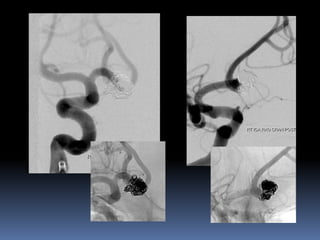

Classical blister aneurysm

34-year M, SAH

38 yr oldmale patient, 2-day old SAH Known hypertensive Clinically grade II Small Blister/dissecting Friable, continued growth, re-rupture